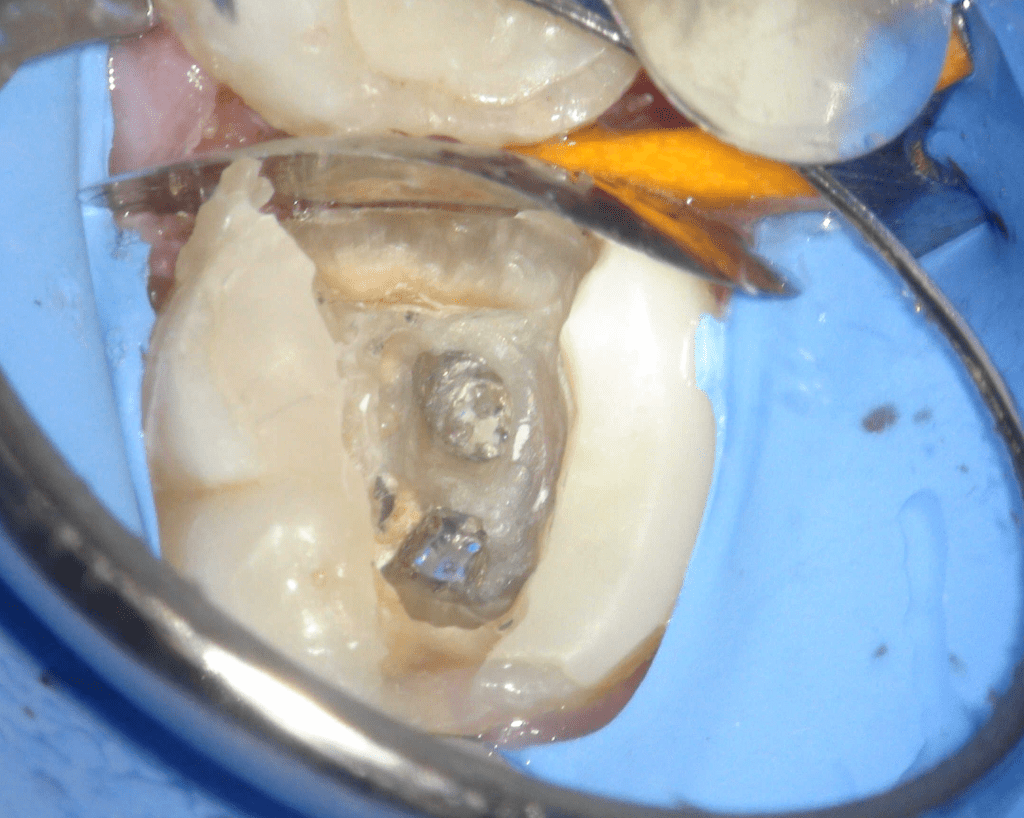

Pulpotomía biodentine + reco preendio